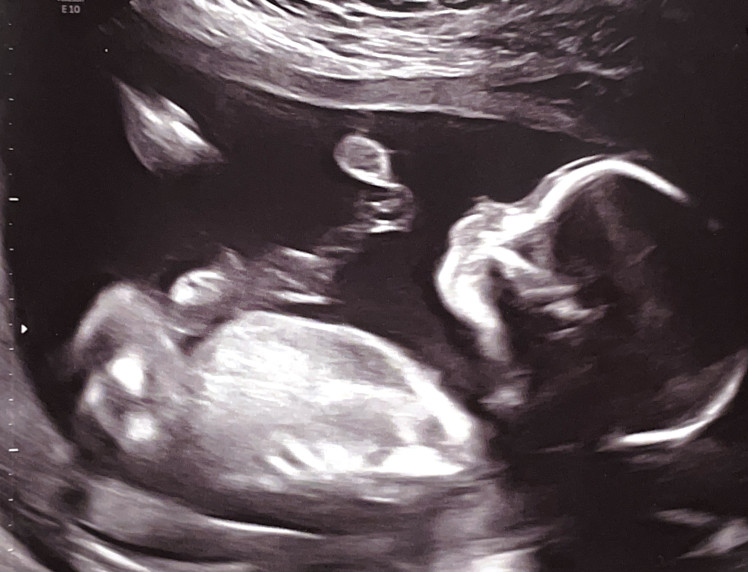

We walked into the ultrasound room, filled with a mixture of excitement and apprhension, hoping that our child would be viable. Lili lay down, and the technician got to work. “The jelly is warm!” Lili commented, pleasantly surprised that it wasn’t freezing cold. The first image of our child was projected on the screen before us, and we couldn’t stop smiling. One by one the technician catalogued the baby’s parts, their humeri, femurs, the valves of the heart, the fingers, the toes, the brain, the spine, and more–we got to see it all. Our hope bloomed and meshed with reality. The baby was fine. And wiggled a lot. It was positively magical to watch.